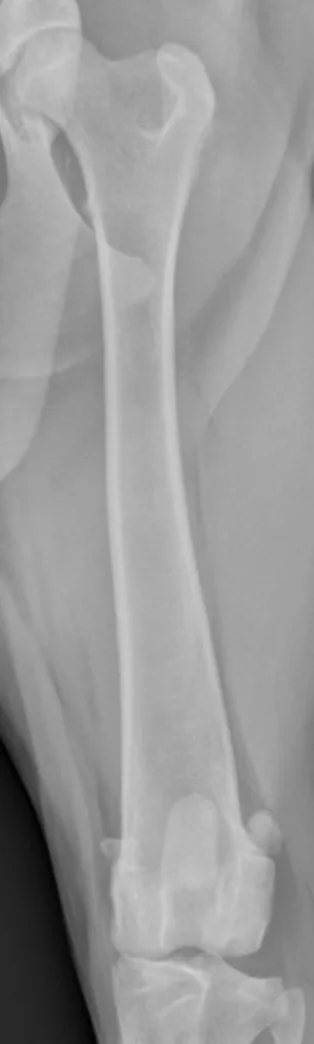

Place the patient in dorsal recumbency. Center the abdomen over a V-trough sponge positioner to keep the body straight; ensure the pelvis and caudal abdomen are outside of the trough. Pull the pelvic limb caudally into full hip extension, and manually hold (or tape down) the limb. Once the pelvic limb is completely extended, rotate the stifle slightly medially to align the femur. Center the patella within the patellar groove, facing toward the ceiling. Radiograph each femur individually.

Center the collimator beam over the femur so the laser alignment line runs parallel to the femoral diaphysis.

Hip pathology (eg, osteoarthritis) can limit hip extension and result in foreshortening of the femur. A horizontal-beam radiograph positioned perpendicular to the femoral diaphysis can be used in these situations.

With a straight craniocaudal femoral radiograph, the tip of the lesser trochanter should be visible on the medial side of the proximal femur (A); the medial (B) and lateral (D) fabellae should be equally positioned over the medial and lateral femoral cortices, but there can be some variation among patients. The patella (C) should be centered over the distal femur, and both sides of the intercondylar notch should be parallel and visible (parallel lines).